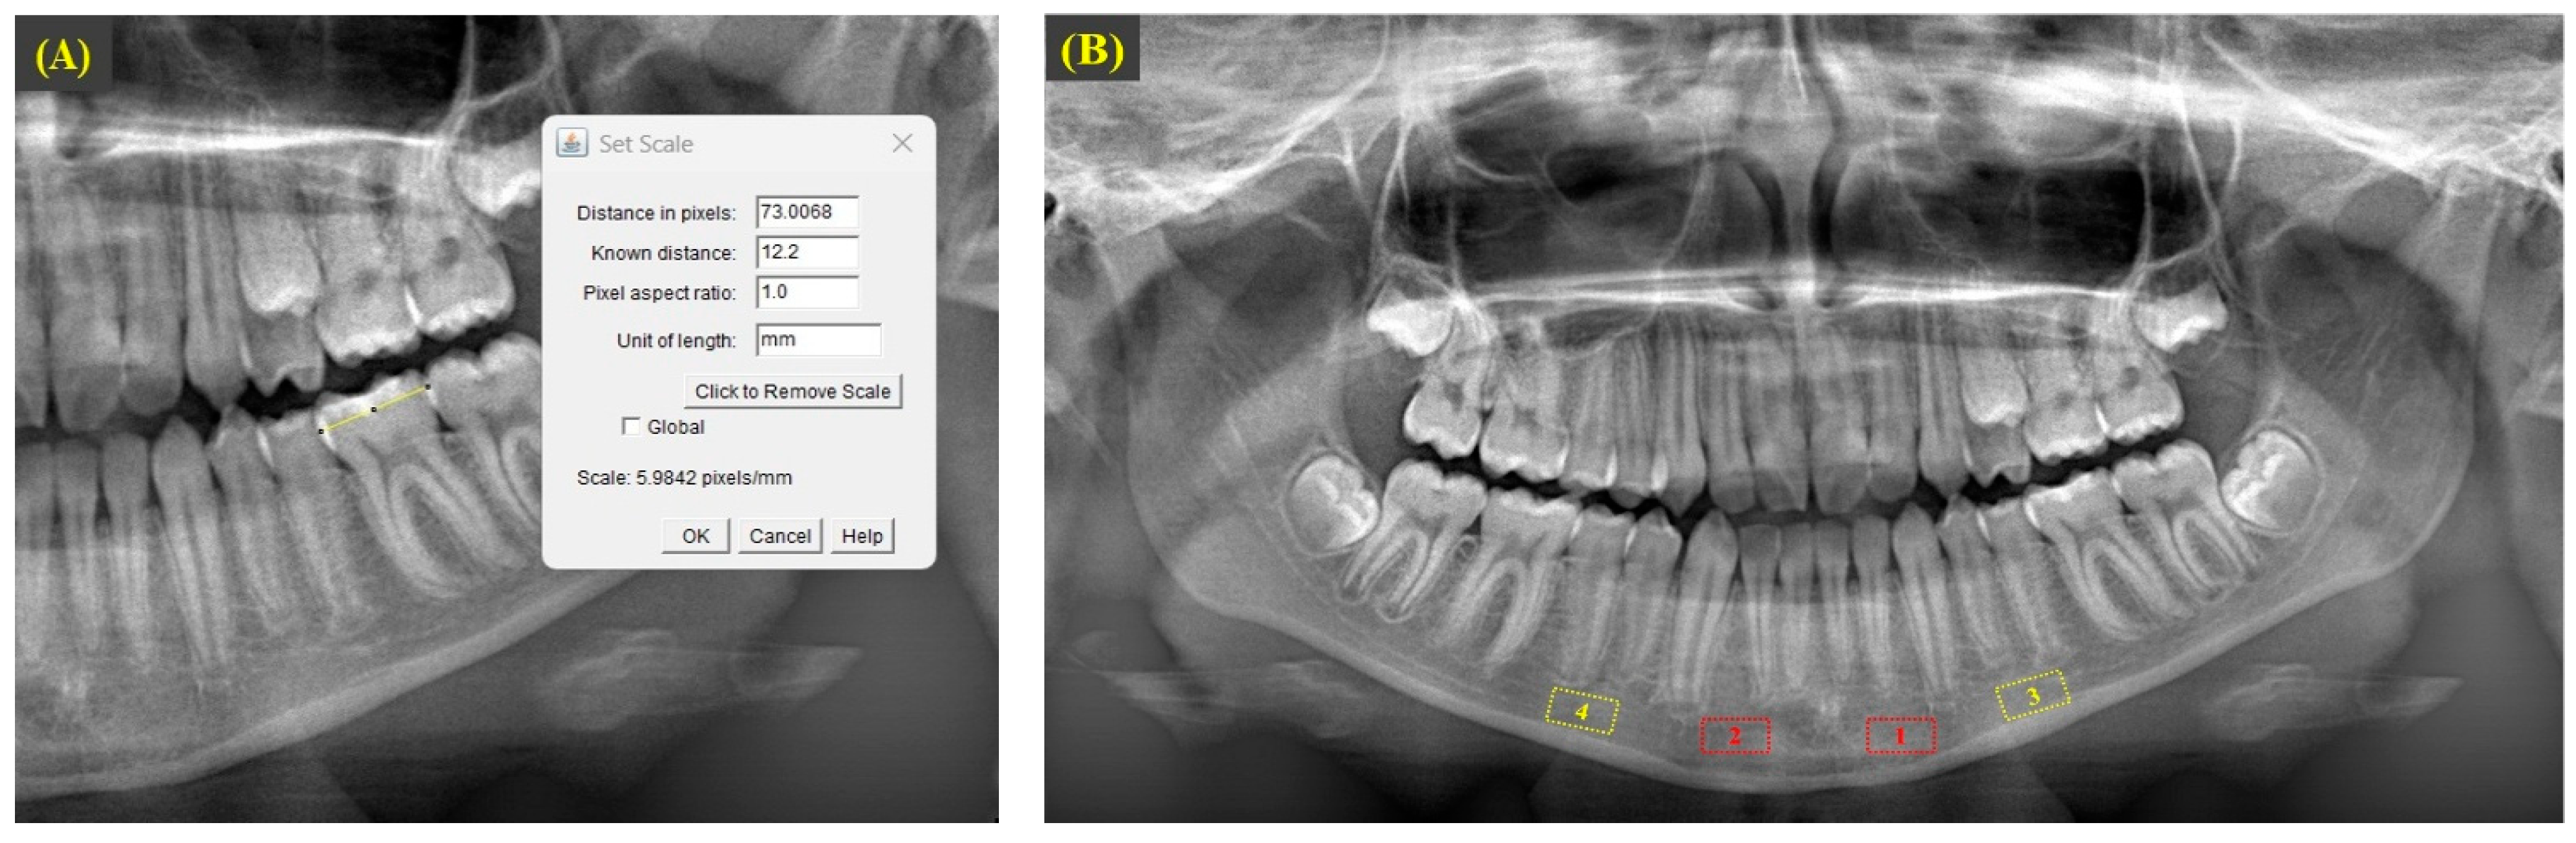

2.5. Fractal Dimension Analysis